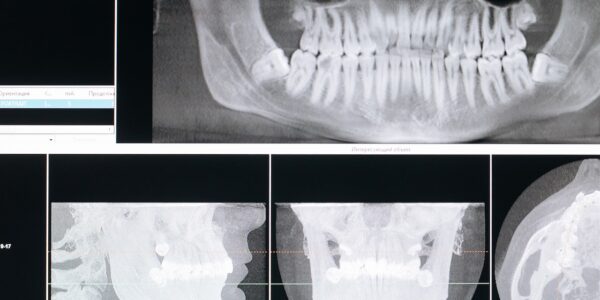

Implanty – skuteczny sposób na walkę z ubytkami zębowymi

Implanty zębowe to bardzo skuteczny i bezpieczny sposób naprawy ubytków w uzębieniu. Żeby odzyskać piękny uśmiech i dobre samopoczucie w kwestii zdrowia jamy ustnej, wiele osób decyduje się na zabieg wszczepienia implantu zębowego. Czym jest implant zębowy? Implant zębowy jest…